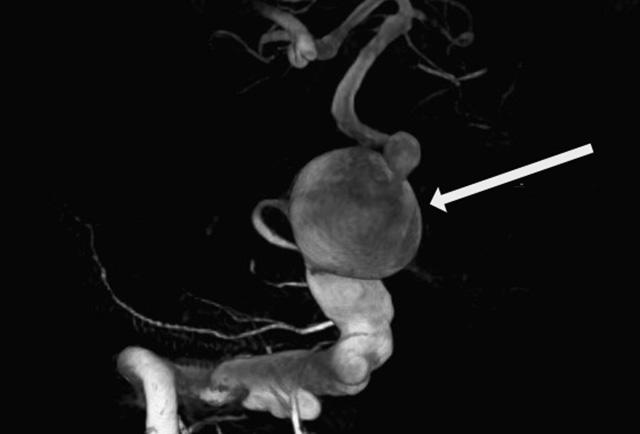

“Our study is the first to identify a genetic cause for a sporadic aneurysm,” Ferreira said. “I suspect we’ll find other types of aneurysms have a genetic cause as well.” .In the study, researchers began with the case of a young man who started to develop aneurysms at an early age. Genetic evaluations at major medical centers around the country had failed to find mutations typical of the inherited disorders associated with aneurysm. The type of aneurysm this patient developed are called fusiform, which means or spindle-shaped, because they tend to be wide in the middle and taper at the ends. These are unlike the much more common form of aneurysms, saccular aneurysms, which form spherical, balloon-like bulges on the side of the blood vessel.